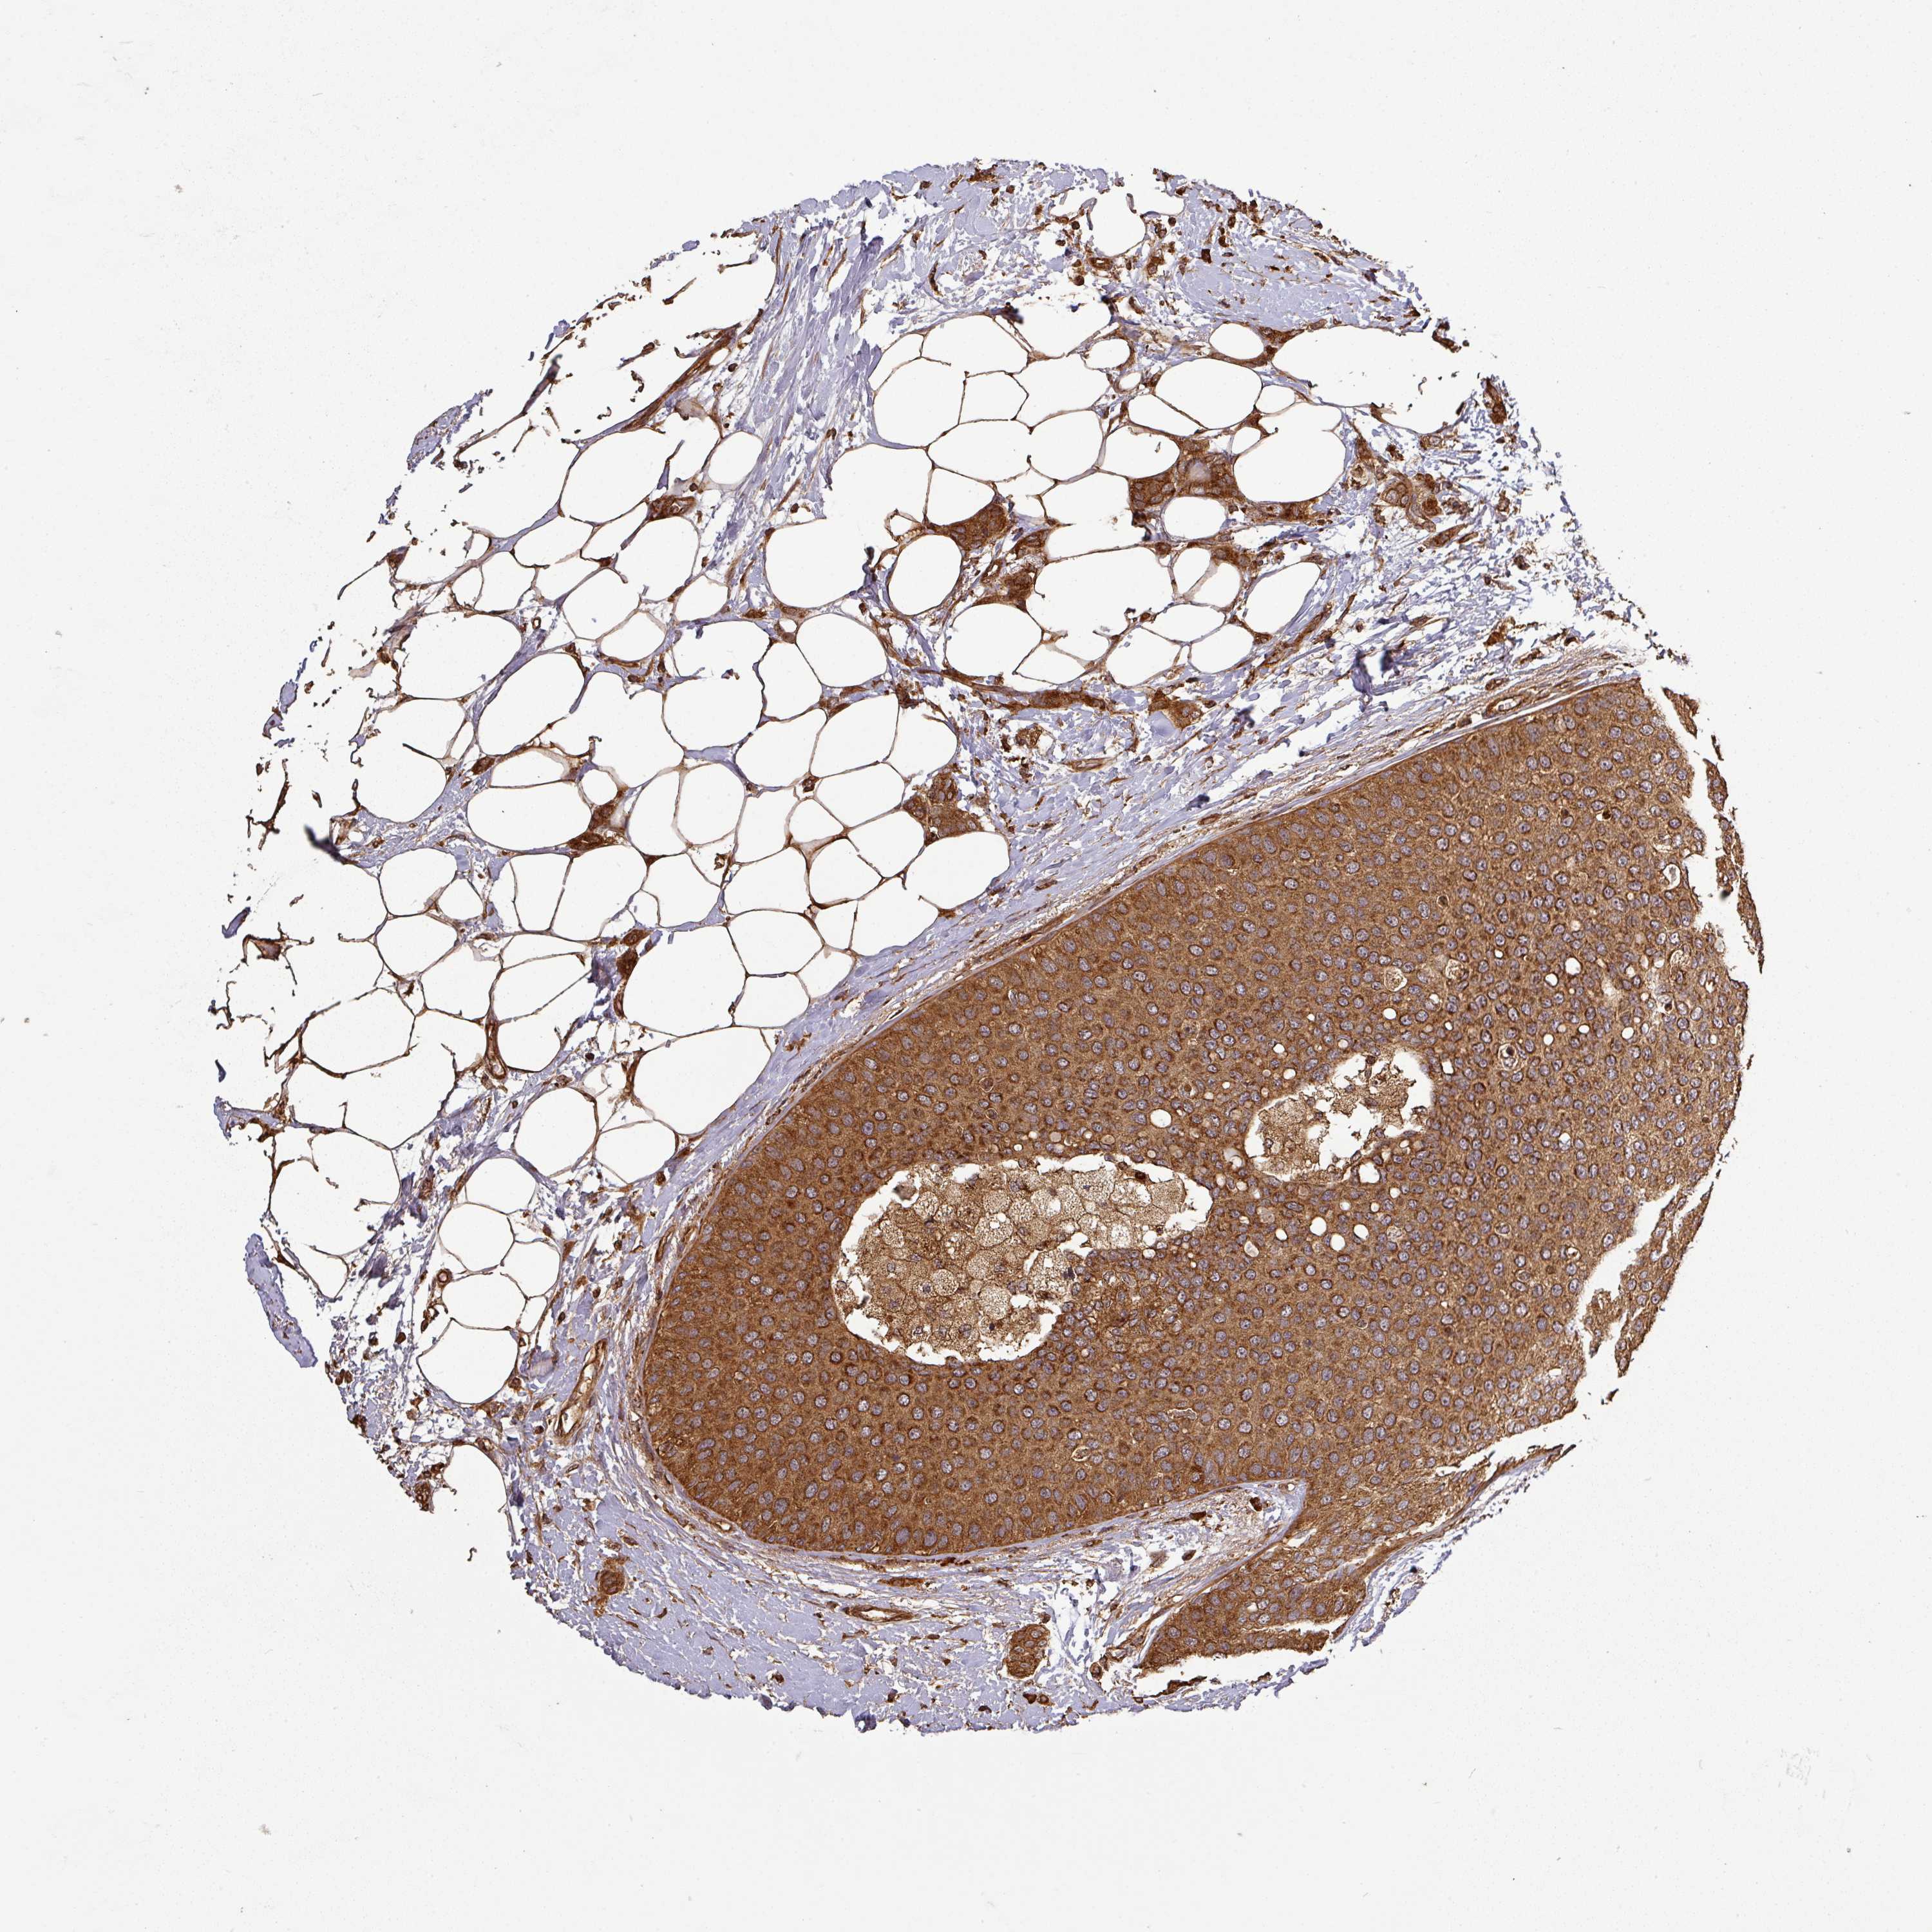

Breast cancer

Human cancer